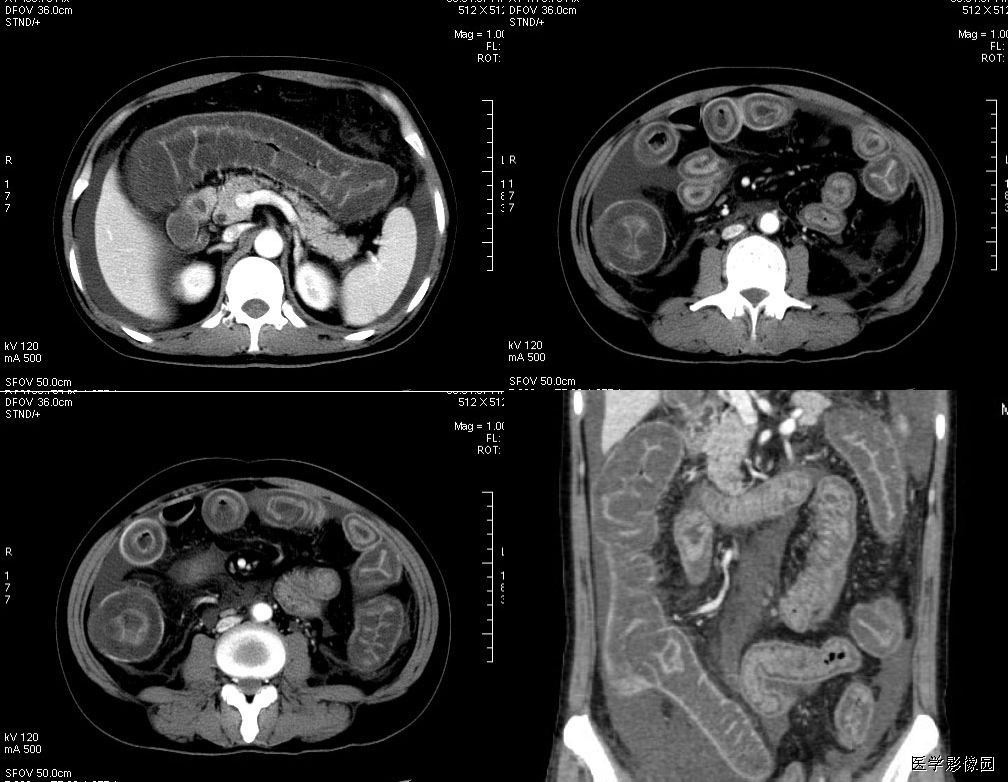

5、肠系膜混浊征

肠系膜脂肪受炎症细胞、液体(水肿、淋巴液和血液)、肿瘤浸润及纤维化的CT表现。当肠系膜被液体或细胞浸润时,其脂肪CT值增加到-40~ -60HU(肠系膜脂肪的CT值类似于皮下及腹膜后脂肪,约-100~-160hu,肠系膜血管常呈横行或断面显示。),动、静脉失去锐利边缘。根据浸润的性质和范围,肠系膜血管可部分或完全模糊,顺着脏层腹膜常能发现肠系膜疾病的线索,在周围脂肪衬托下,肠系膜病变显示更加清晰。

上两幅图:肠系膜上动脉栓塞

下两幅图:十二指肠扭转致肠壁增厚、肠系膜水肿